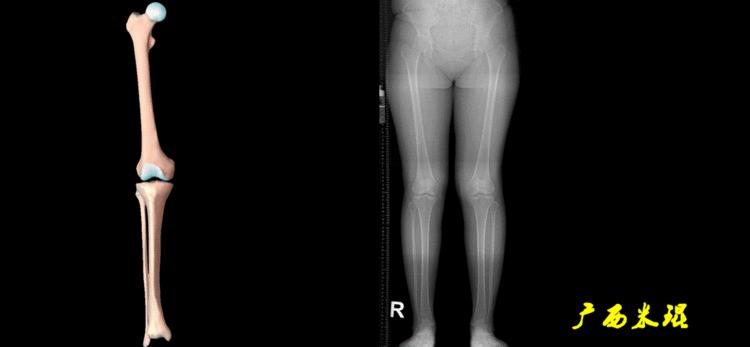

四、下肢全长片测量的意义

1、判定有无畸形

下肢的畸形定义为生理轴线的偏移。关节角和轴线在冠状面、矢状面和横断面上可发生病理改变,并引起整个下肢的对线异常。

最常见的下肢畸形发生于冠状面,即膝内外翻畸形,冠状面的对线异常通过应用“对线异常检验”进行分析,机械轴的偏移(MAD)表现为对线异常。

膝内翻是指下肢力线通过膝关节中心点内侧,距中点2mm以上,偏内超过15mm为显著膝内翻。膝外翻是指下肢力线通过膝关节中心点外侧,距中点2mm以上,偏外超过10mm为显著膝外翻。

2、判断畸形的部位

画出下肢全长片中的机械轴和力线轴,确定畸形来自股骨、胫骨还是关节内。首先我们确认股骨机械轴及mLDFA,超出范围为股骨畸形;然后我们确认胫骨机械轴及MPTA,超出范围为胫骨畸形;最后我们确认关节线的汇聚关系JLCA,超出范围为关节内畸形。